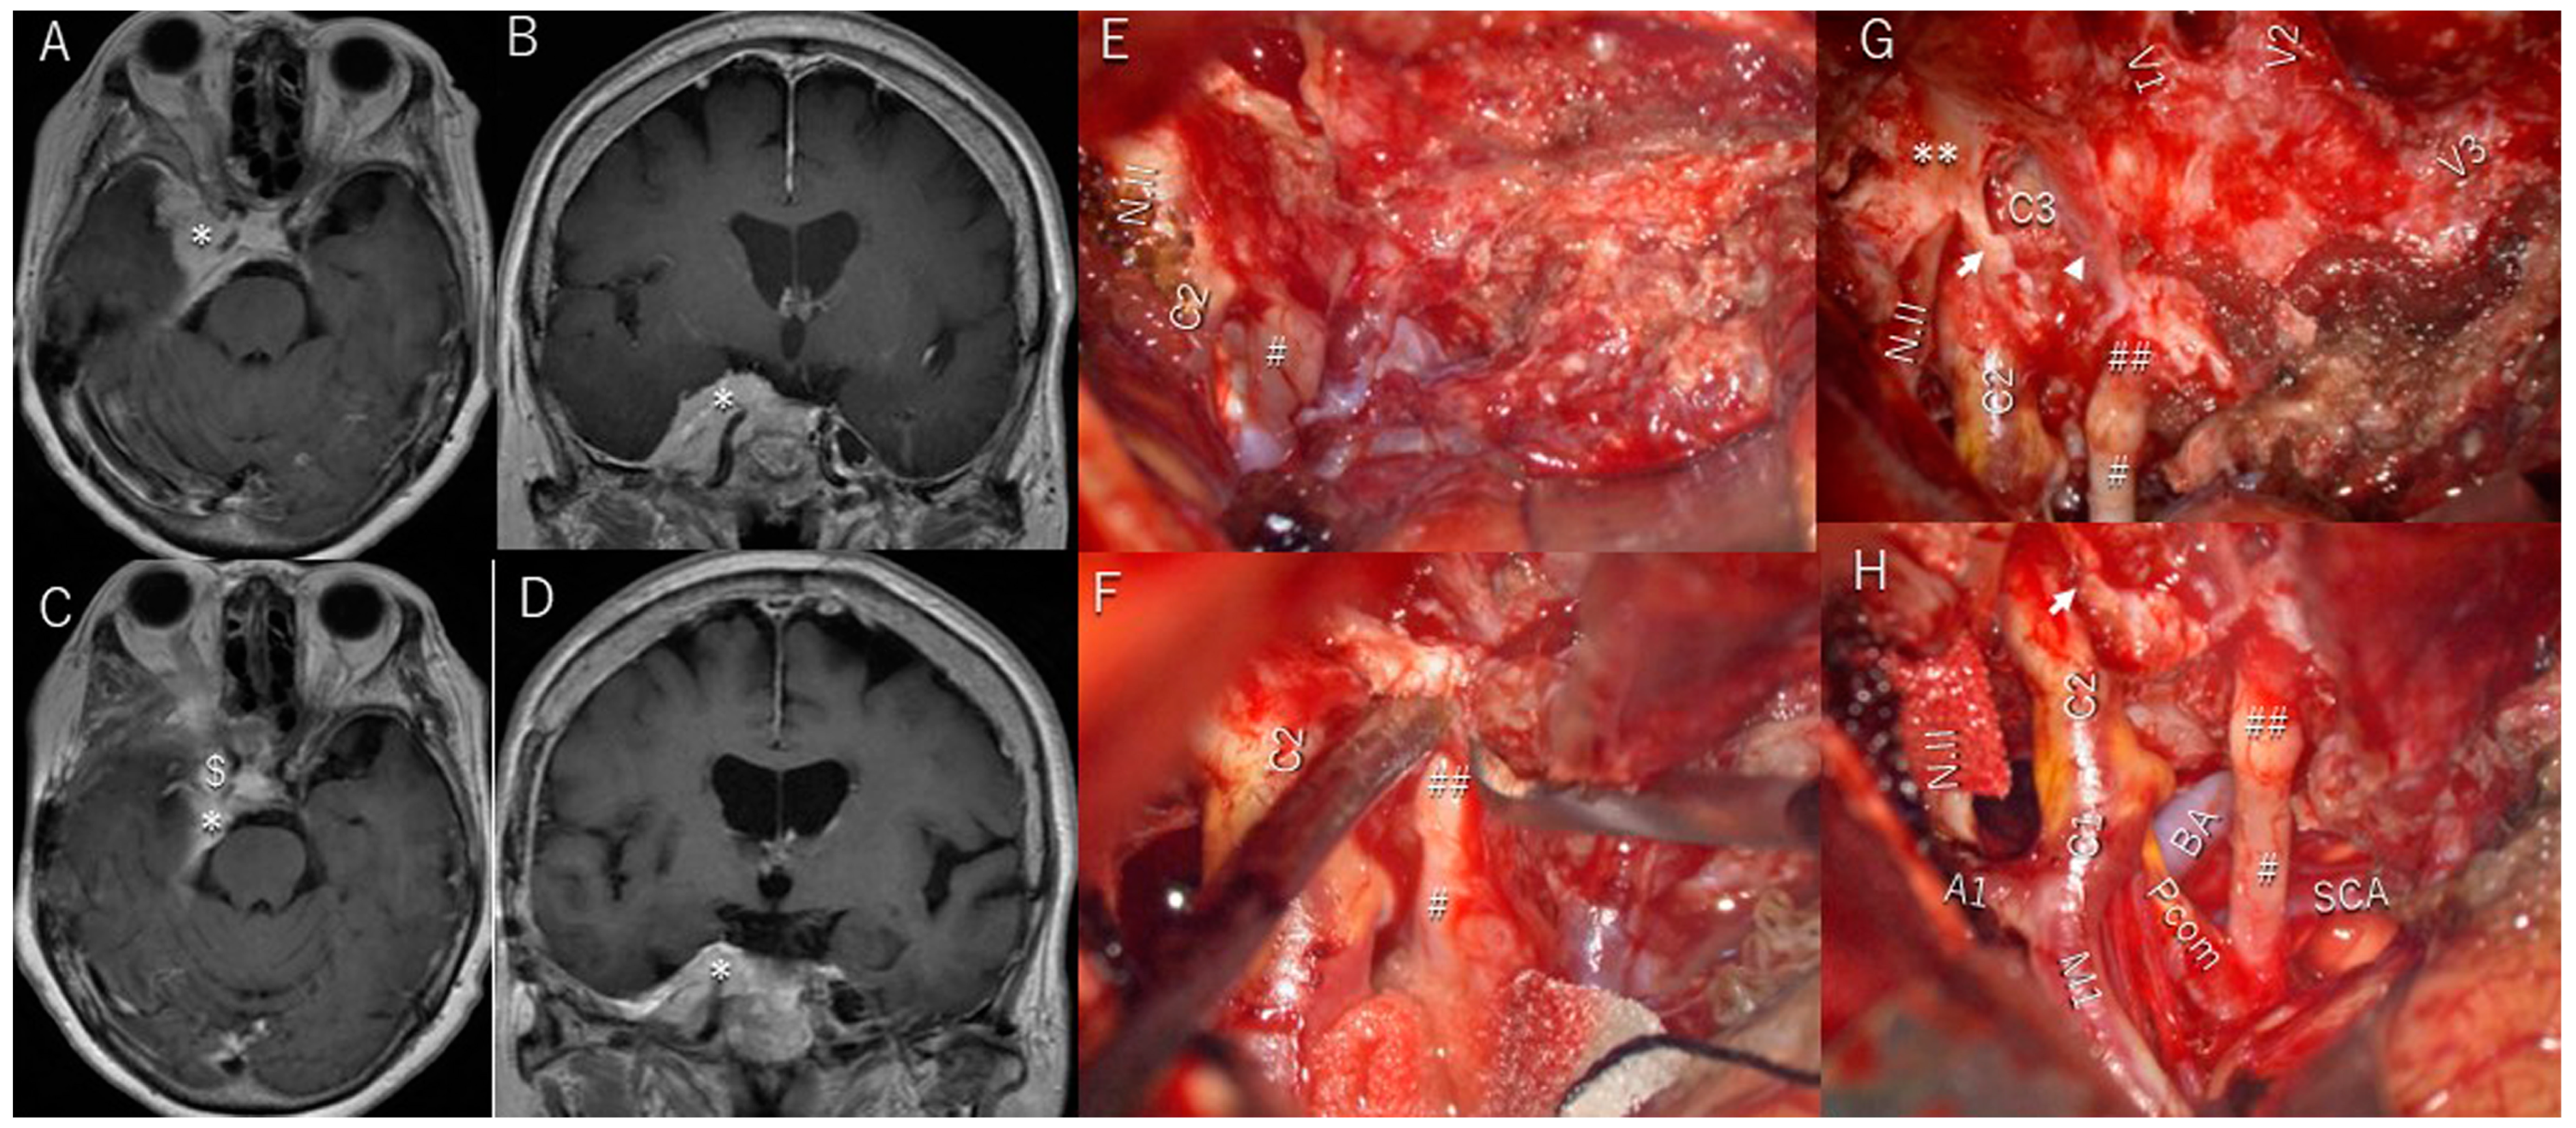

3.6. Illustrative Patient Cases

| 1 | y | y | entire lateral wall of cavernous sinus | Totally with sacrifice of all cranial nerves | 4 | y/no change | y/sacrifice | y/sacrifice | brain stem swelling/complete recovery | |

| 2 | y | y | lateral triangle | Slightly | 4 | y/almost complete recovery | y/complete recovery | y/complete recovery | ||

| 3 | y | y | lateral triangle | Slightly | 3 | y/almost complete recovery | n | n | ||

| 4 | y | y | Parkinson triangle | Slightly | 3 | y/slightly improved | y/complete recovery | n | ||

| 5 | y | n | anterolateral triangle | Totally | 1 | n | n | n | brain swelling/complete recovery | |

| 6 | y | n | Parkinson triangle | Slightly | 4 | y/complete recovery | n | n | brain swelling/complete recovery | |

| 7 | y | n | Parkinson, anterolateral, lateral triangle | Partially | 3 | y/complete recovery | y/complete recovery | y/complete recovery | exophthalmos/complete recovery | |

| 8 | y | n | Parkinson, anterolateral, lateral triangle | Partially | 3 | y/slightly improved | y/almost complete recovery | y/almost complete recovery | facial dysesthesia/almost complete recovery | |

| 9 | y | y | anterolateral, paramedial, lateral, Parkinson triangle | Subtotally | 4 | n | y/complete recovery | y/complete recovery | facial dysesthesia/almost complete recovery | |

| 10 | y | n | Parkinson triangle | Partially | 4 | n | y/worsened. | y/worsened. | ||

| 11 | y | y | paramedial, Parkinson, lateral, anterolateral triangle | Subtotally | 4 | y/complete recovery | n | y/slightly improved | ||

| 12 | y | y | anterolateral triangle, | Partially | 4 | n | y/complete recovery | n | exophthalmos/complete recovery | |

| 13 | y | y | anterolateral triangle | Partially | 4 | n | y/complete recovery | n | ||